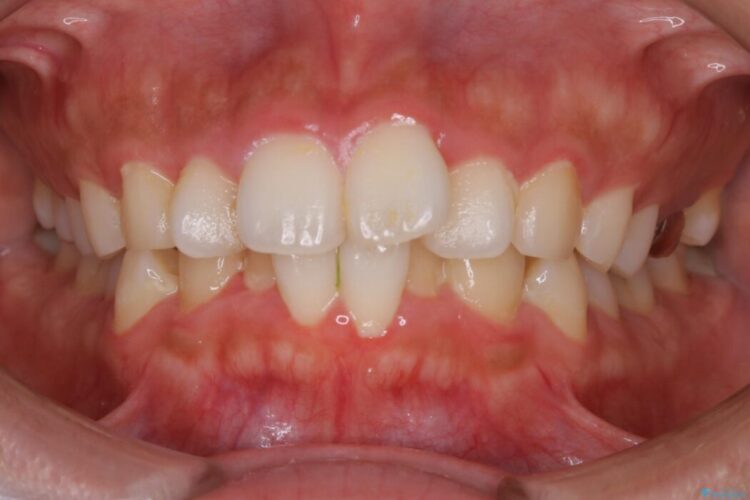

口ゴボに加えて歯列のガタガタを改善したいと来院されました。

口元が後方に下がったことにより横から見たEラインが改善し、口元の印象が変わったと患者様にとても喜んでいただけました。